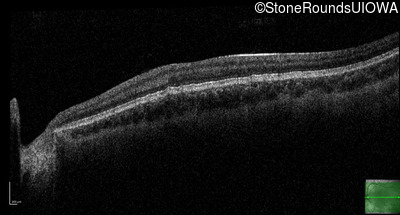

Optical Coherence Tomography - Left - 20/160 +1

Exemplar / OCT Stack

OCT Stack